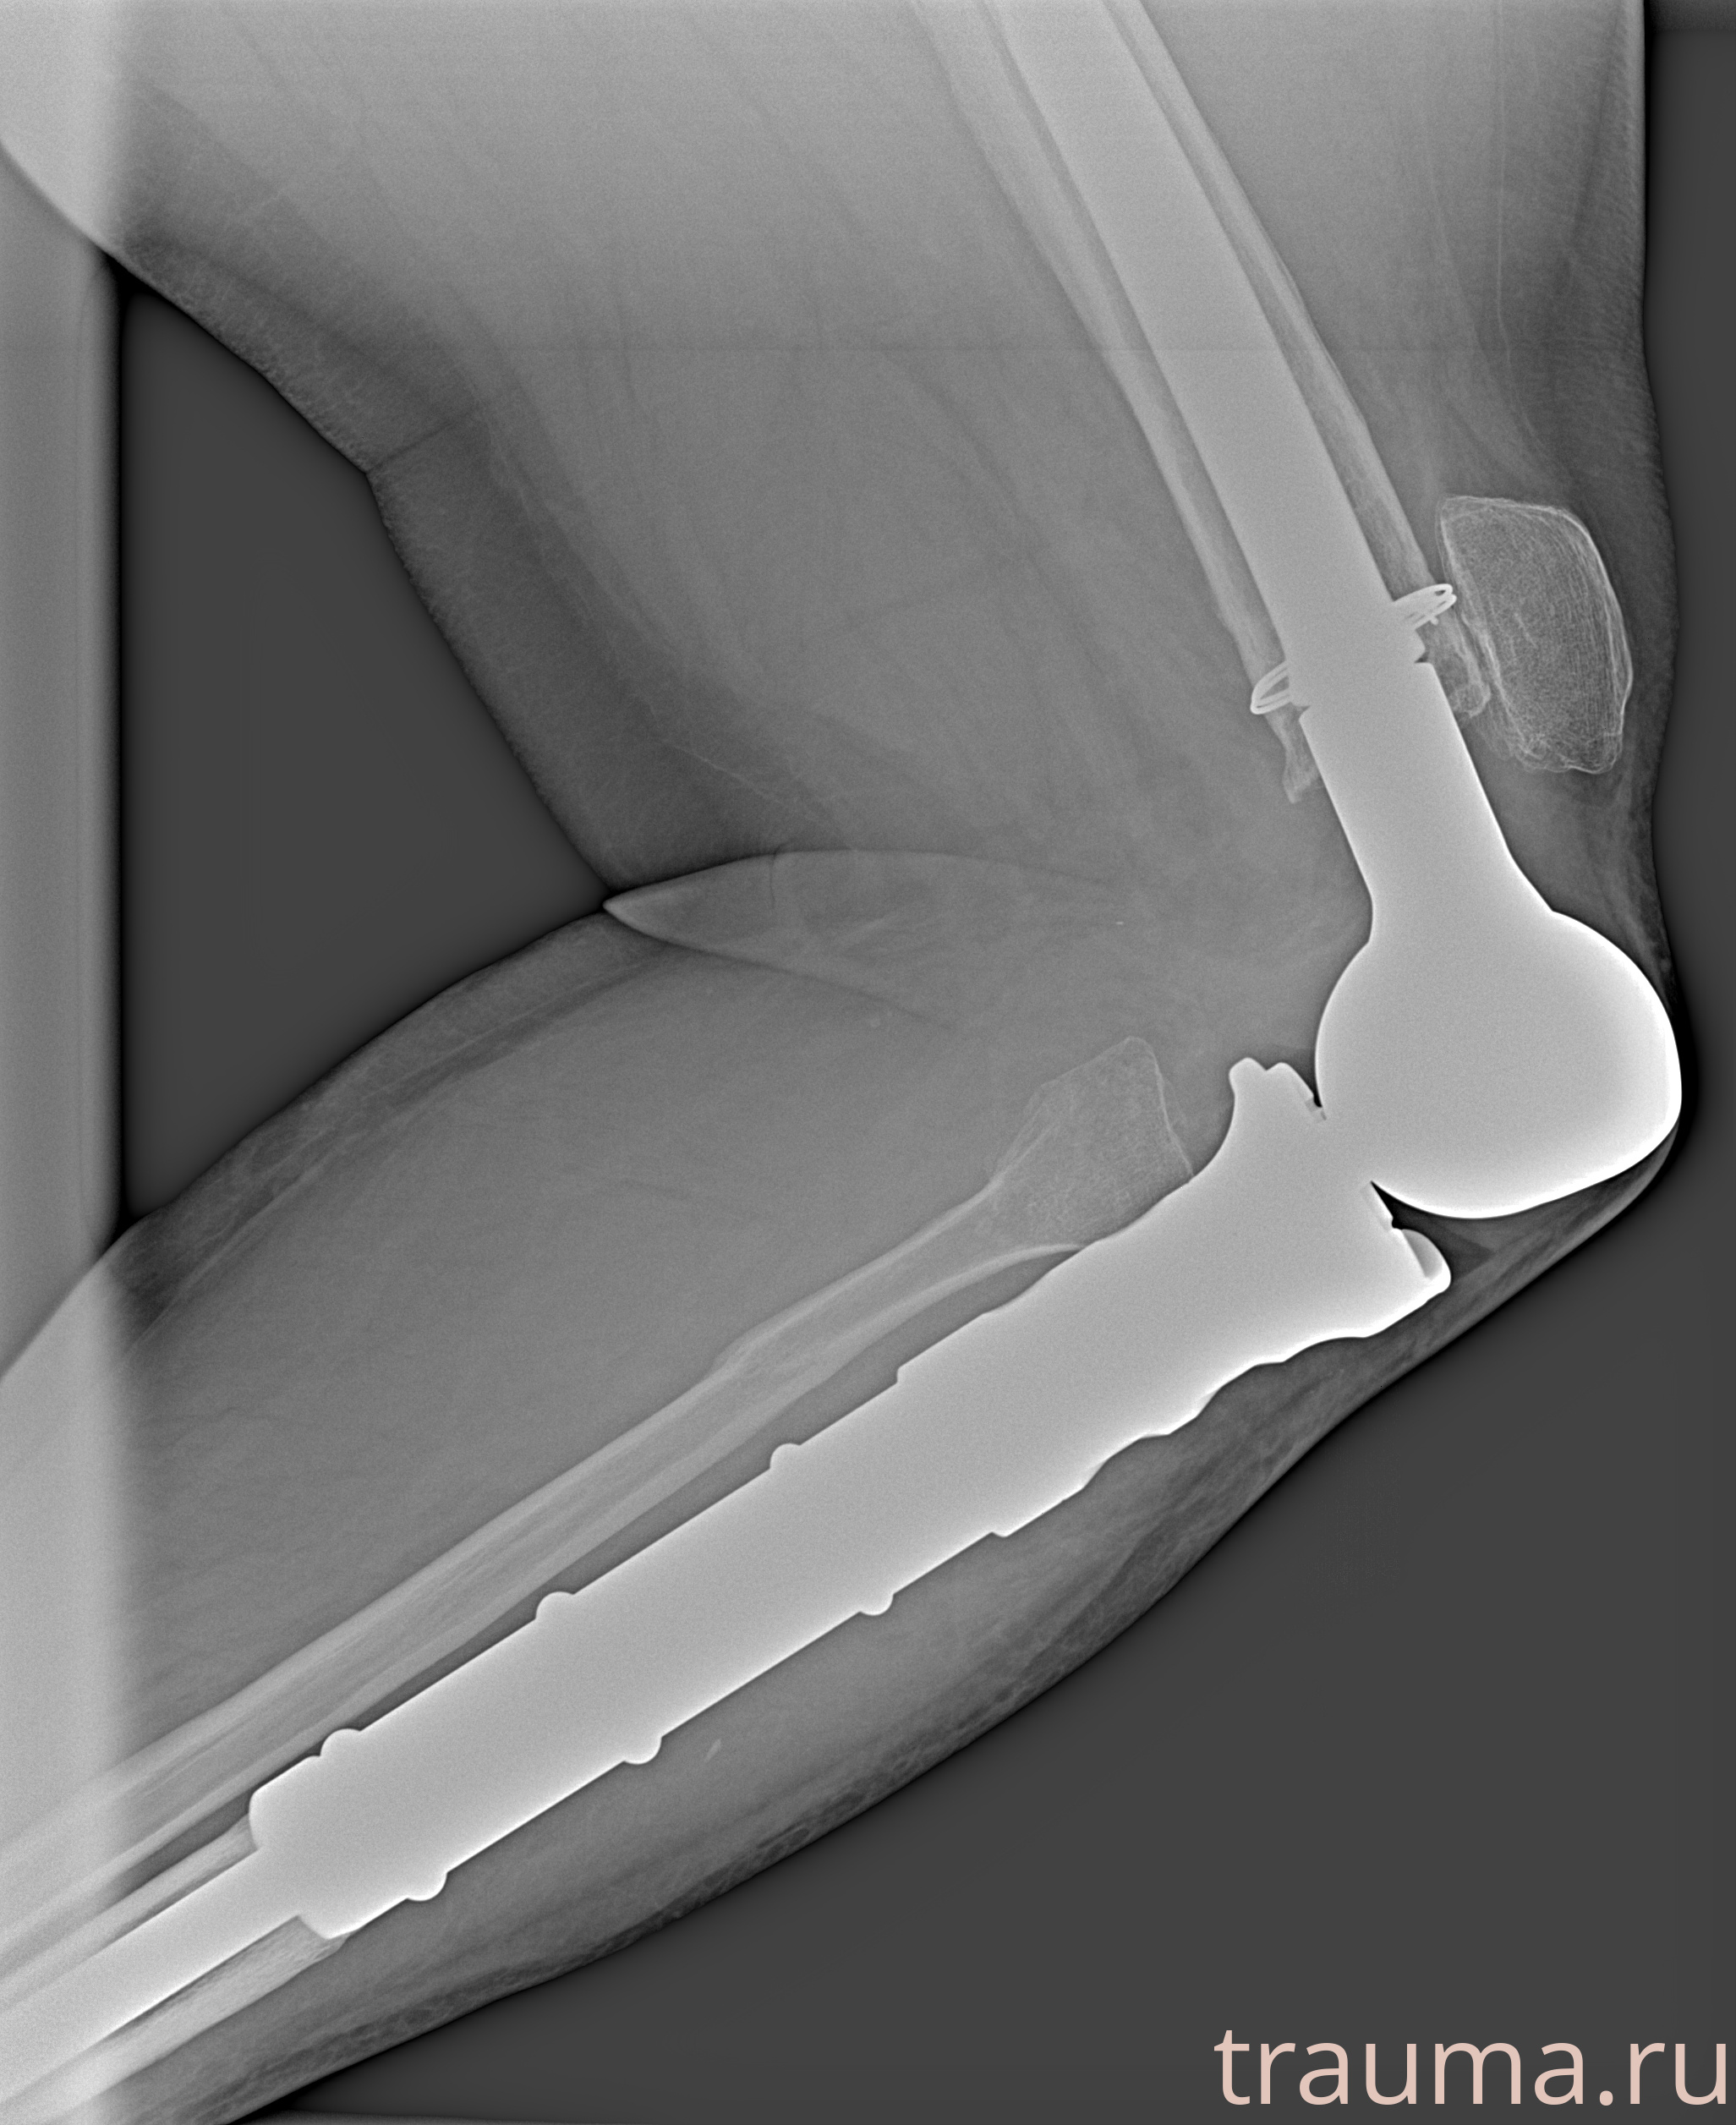

Рентгенограммы

Рентген на дому: по вашему адресу приезжает врач-рентгенолог, травматолог-ортопед с мобильным рентгеновским аппаратом, проводит диагностику травмы или заболевания, делает необходимые рентгенограммы, дает рекомендации по дальнейшему лечению. Получить качественные снимки в домашних условиях возможно благодаря уникальной методике, разработанной МосРентген Центром для института  Склифосовского